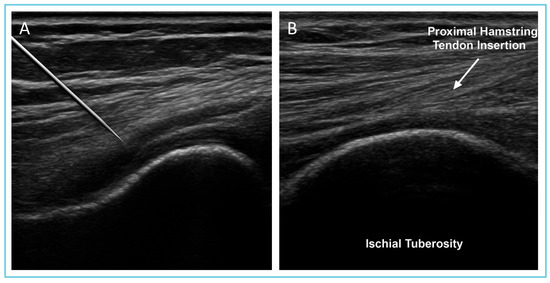

The procedures were performed by a specialist in musculoskeletal pathology through an ultrasound machine. The correct deposition was confirmed via ultrasound and MRI imaging (Figure 1).

Figure 1.

Ultrasound-guided injection of MD-Muscle (porcine collagen) in the proximal hamstring region. (A) The physician uses an ultrasound probe for real-time needle guidance to ensure precise delivery into the proximal hamstring tendon. (B) Magnification of image (A) showing the PHT region (arrow) and ischial tuberosity (bottom of the figure). The labeled structures highlight the muscle tissue and the hamstring tendon. This imaging confirms the correct positioning of the needle under ultrasound guidance.